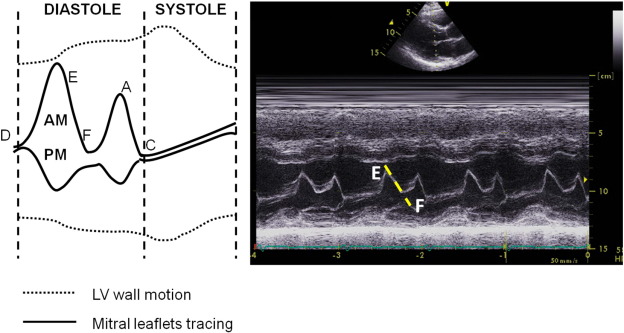

For EF slope measure, recordings were made using leading-edge methods according to the standards suggested by the American Society of Echocardiography [12]. The manual tracing of anterior mitral leaflet closure after rapid early filling was displayed by M-mode imaging, and was determined by drawing a line from the E to the F point (Fig. 1) by a single experienced technician. A steeper EF slope (unit: mm/s) represented rapid and normal filling of LV during the early diastolic phase while a more damped and slowed slope pattern was observed in subjects with impaired LV diastolic function [13]. The intra- and inter-observer variability (coefficient of variance) for LV wall thickness, diastolic diameter and M-mode based EF slope measurement from a random set of 30 subjects in our laboratory was 7.2%, 6.1% and 5.8% and 7.4%, 6.8% and 6.2%, respectively.

Illustration of individual landmarks (A, C, D, E and F points) of a ...

Fig. 1.

Illustration of individual landmarks (A, C, D, E and F points) of a transthoracic parasternal long-axis M-mode tracing (left panel) and a representative EF slope from a manual tracing (right panel).